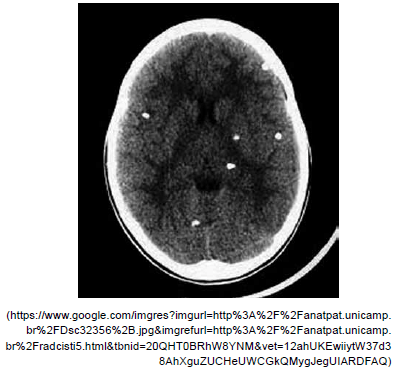

Paciente masculino, 26 anos, admitido com crises convulsivas generalizadas de início há dois dias. Tomografia de crânio a seguir. Assinale a alternativa correta quanto ao diagnóstico mais provável nesse caso.